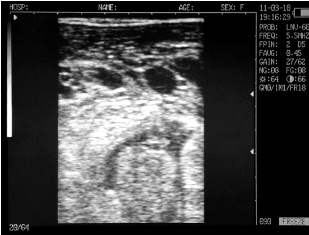

Ultrasound images of cows reproductive system, generated by a scanner Sonovet with rectal linear transducer.

Ovary cows in mid-cycle

Corpus luteum in the ovary of the cow